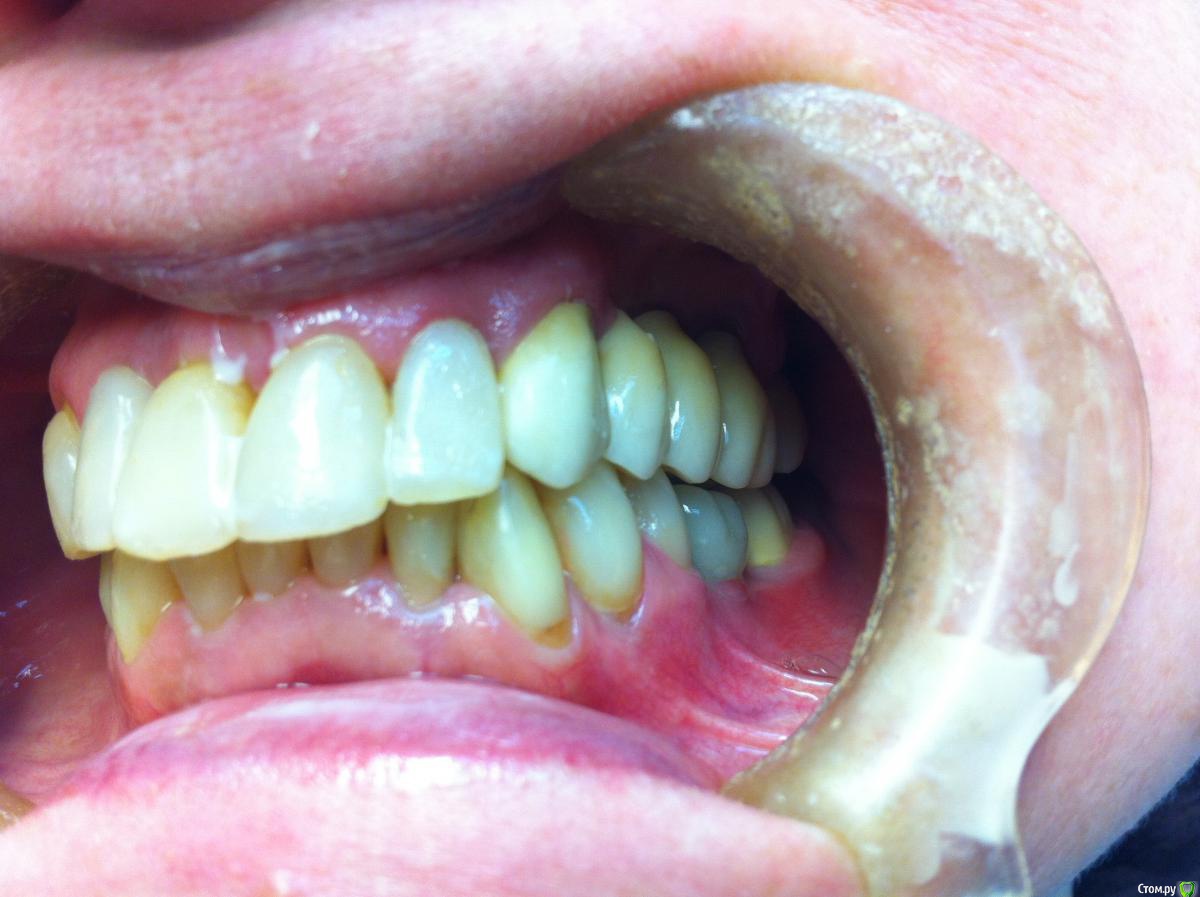

Айнур Фаязович Опубликовано 2 декабря, 2015 Поделиться Опубликовано 2 декабря, 2015 Пациентка обратилась с целью замены временной коронки на имплантате 36 на постоянную конструкцию. В ходе сбора анамнеза удалось выяснить, что 3 года назад у нее на 36 зубе произошла поломка винта внутри имплантата и, как следствие, появилась подвижность этой коронки. Ее доктору, у которого она протезировалась, удалось извлечь винт, но пришлось делать новую резьбу. Теперь она обратилась ко мне. Прилагаю фотографии полости рта, рентгеновские снимки до поломки винта, на момент обращения ( снимок с временной коронкой) и с трансфером для открытой ложки без винта (узкая платформа Астра). Дело в том, что у пациентки временная коронка на стандартном титановом абатменте ( платформа узкая 3,5-4,0) был зафиксирован с помощью винта от Dentium, при этом область шестигранника расширена изнутри ( чтобы проходил винт от Dentium) Но теперь возникают вопросы: 1)Как снять слепок с трансфером для узкой платформы, если родной винт не держится из-за изменения конфигурации резьбы, винт для широкой платформы и даже винт для Dentium слишком велики по размеру?2)Допустимо ли, по-вашему, менять конфигурацию постоянного абатмента в области шестигранника, расширяя его изнутри, чтобы проходил винт?3)Стоит ли проводить замену временной коронки на постоянную, если на рентгеновском снимке довольно серьезные повреждения в верхней части имплантата после изменения конфигурации резьбы. Уважаемые коллеги, если кто сталкивался с подобным, буду признателен за ваши варианты решений данной пробемы. За качество снимков прошу прощения, снимал на телефон. Ссылка на комментарий